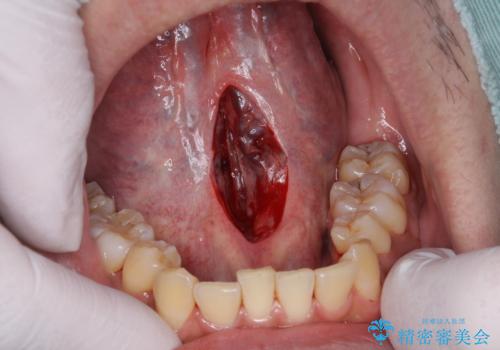

舌の動きを制限してしまう下部のヒダが長い状態を改善する、舌小帯の形成を即日で行い滑舌の改善を計画します。

舌小帯の形成は10分程度で終わる小手術です。